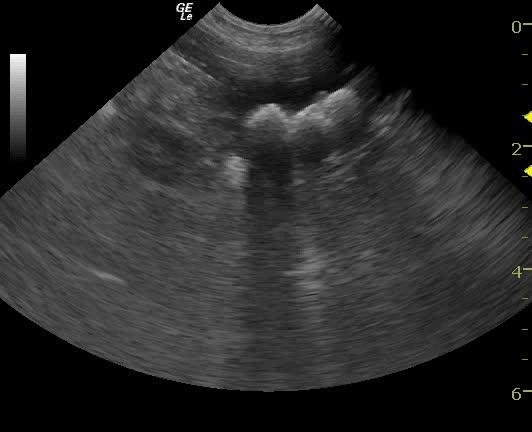

An 11-year-old SF Bichon dog was presented with a history of 3-4 days of lethargy, anorexia, and vomiting. Abnormalities on physical examination were tense abdomen, mild dehydration, and moderate dental tartar. Urinalysis (free-flow sample) showed inappropriate SG, (1.017), hematuria, and, pyuria. Abnormalities on CBC and serum biochemistry were leukocytosis, monocytosis, neutrophilia, azotemia, and hyponatremia.